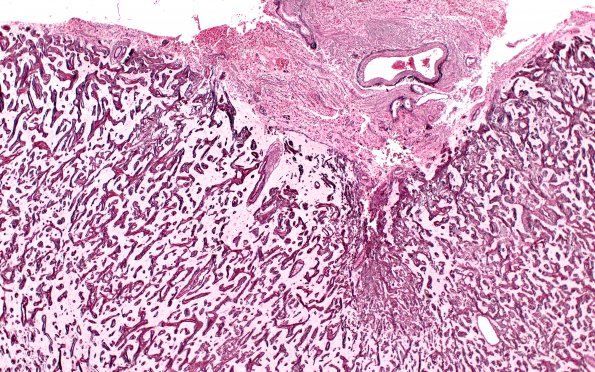

Washington University Experience | DEVELOPMENTAL MALFORMATIONS | Meningioangiomatosis | 7H2 Meningoangiomatosis (Case 7) Retic 4X

The series of images shows an unusual pattern of reticulin in meningioangiomatosis, broadly staining the fibrous coarse trabeculae as well as delicate processes in the superficial cortex which may reflect the elements of the Virchow-Robin spaces. (reticulin)